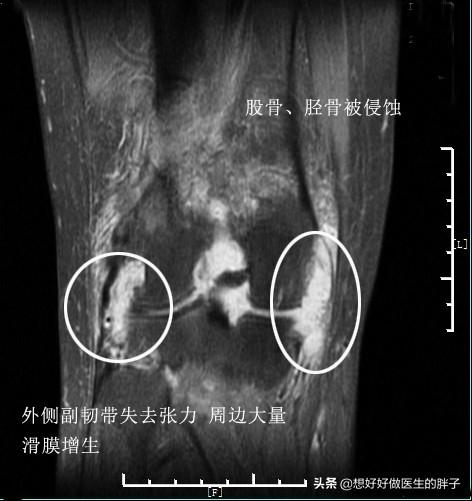

看起来这些病态的滑膜就像是魔鬼的触角一样恐怖,事实也是如此,尤其是对于类风湿关节炎以及痛风性关节炎的患者,这些滑膜会在关节内长久的存在,不断侵蚀关节的软骨以及骨骼。下图就是一例严重类风湿关节炎患者的核磁片子,他的关节软骨以及骨骼看起来已经像是被老鼠啃噬过一样了,这都归咎于类风湿滑膜炎的侵犯!

类风湿关节炎的病理基础就是关节腔滑膜的炎症,病理表现主要有滑膜衬里细胞增生、间质大量炎性细胞浸润,以及微血管的新生、血管翳的形成及软骨和骨组织的破坏等。